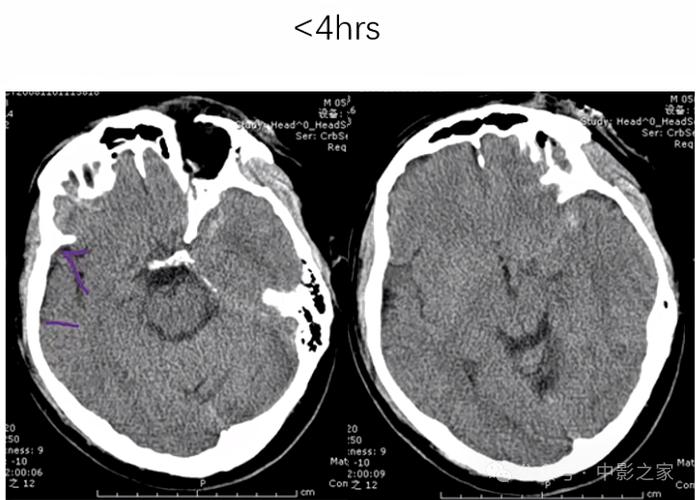

第一阶段:超早期(发病 < 6小时)

- CT表现: 绝大多数情况下,完全正常。

- 医生的解读:

- 好消息: 排除了脑出血,这是最重要的信息!因为如果脑出血,使用溶栓药(如阿替普酶)会致命。

- 挑战: 无法直接确诊脑梗,此时需要结合患者的临床症状(如偏瘫、失语等)和更高级的检查(如MRI-DWI)来确诊。